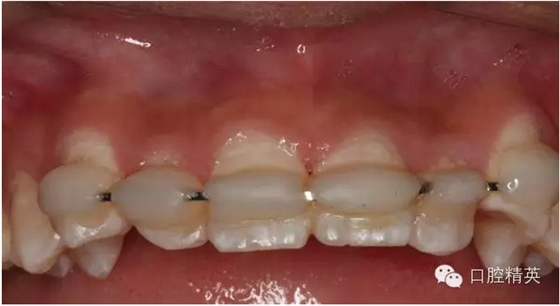

圖6.固定一個月后的唇側(cè)影像,牙齦及粘膜正常?;颊邿o任何自覺癥狀。

圖7.腭側(cè)口內(nèi)像,齦乳頭水腫消失

圖13.拋光完畢的牙面,齦乳頭色澤正常,無牙周袋。21不松動

雖然21離體時間太長,預(yù)后欠佳,愈合方式為骨性粘連。容易出現(xiàn)牙根置換性吸收??梢允菚簳r性,能自然停止,也可以是進(jìn)行性的,直至牙齒脫落,這個過程但起碼維持?jǐn)?shù)年或數(shù)十年。這樣可以保持患側(cè)唇側(cè)豐滿度,又能維持患者到成人階段做永久修復(fù)。不失一種好方法。希望同道多提寶貴意見。共同提高??!